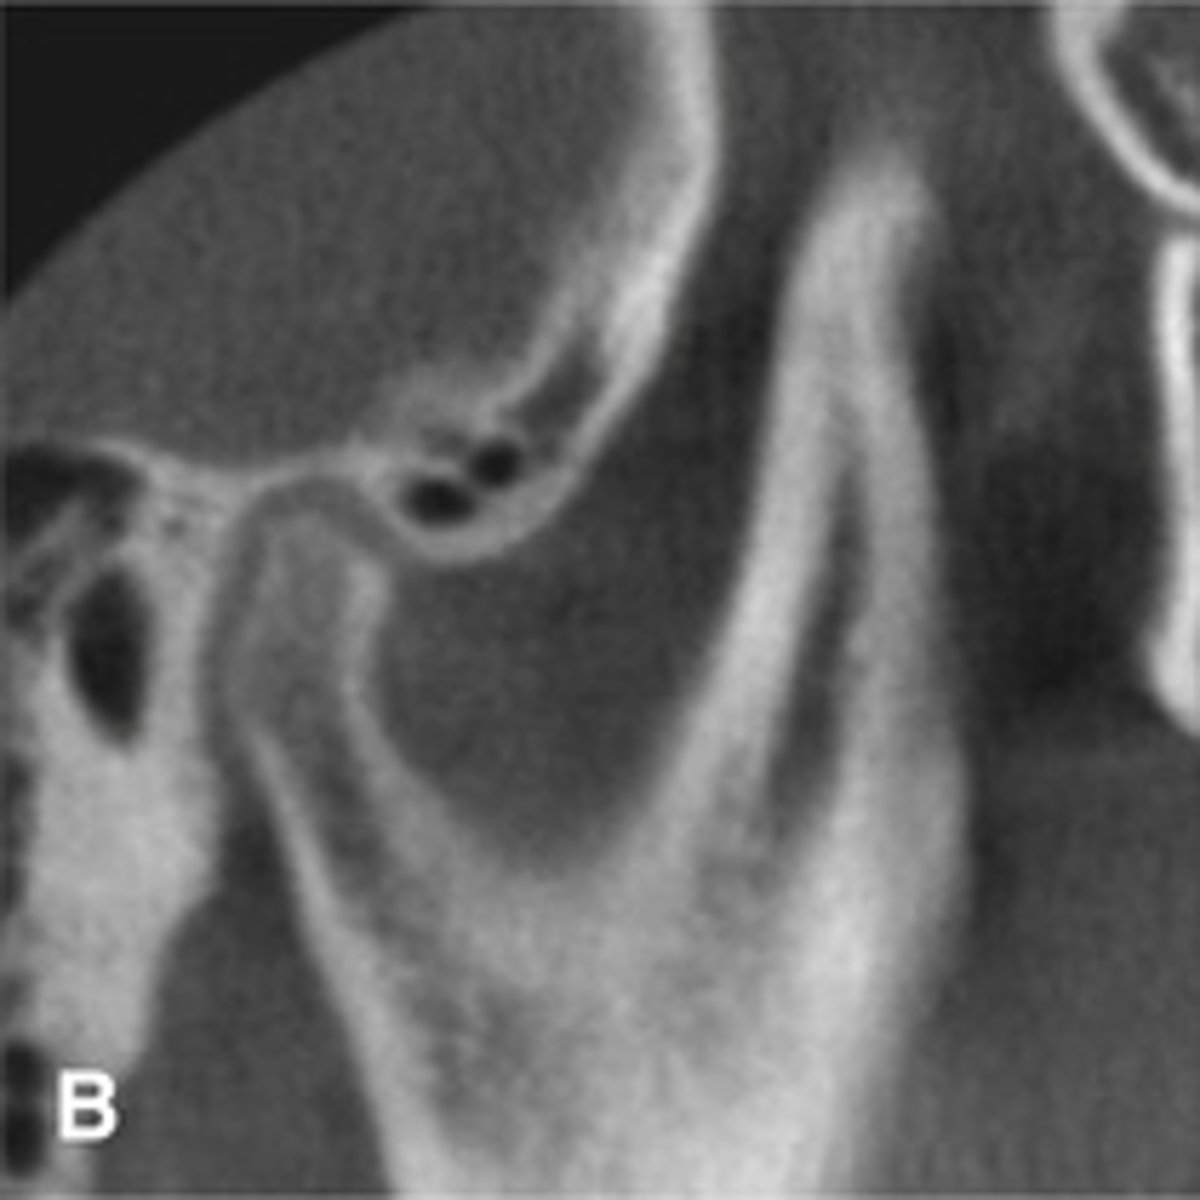

Patient has DJD.

The top images show the subchondral/ Ely cyst, a pseudocyst of connective tissue, granular tissue and osteoid, the bottom images show the same patients left side with broad erosion, a lack of cortication, loss of joint space.

What is the diagnosis of the patient based off these radiographs and what are the features? (Top images = patients right condyle) (bottom images= same patients left condyle)